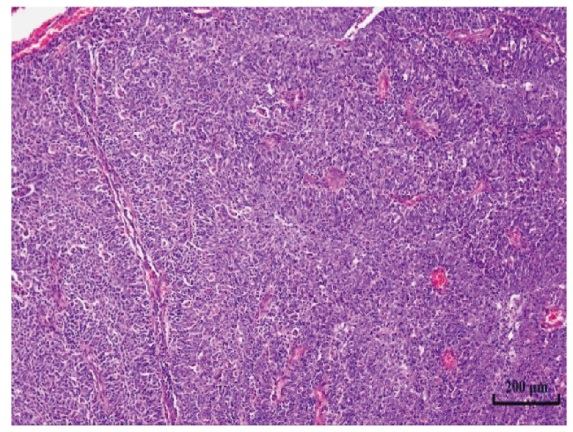

梁静, 张铭, 吴兰, 等. 子宫颈淋巴上皮瘤样癌6例临床分析[J]. 现代肿瘤医学, 2025, 33(10):1764-1770. doi: 10.3969/j.issn.1672-4992.2025.10.017.